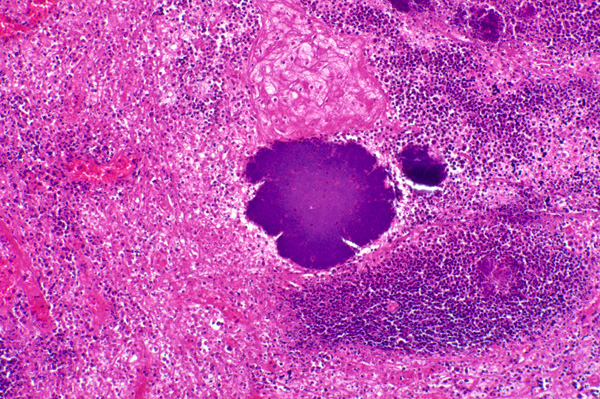

There are scattered variably-sized, large, irregularly shaped, basophilic bacterial colonies.